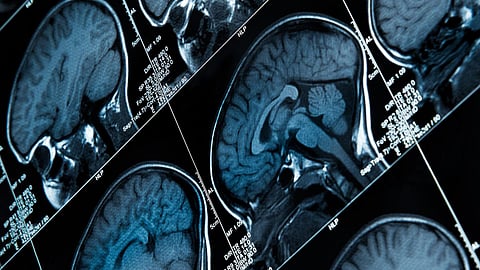

Epilepsy is the most common chronic neurological disorder, with an estimated 5 million people diagnosed with epilepsy globally each year. While it is known to be caused by disrupted electrical activity in the brain, which results in sudden, excessive electrical activity that can lead to abnormal physical and behavioural symptoms, the exact cause of epilepsy is not fully understood. It is believed to be linked to impaired brain development, brain injury, genetic predisposition, and underlying medical conditions such as stroke, brain tumours, and infection. However, without certainty as to the exact cause, people with epilepsy often face discrimination and misunderstanding. To raise awareness on International Epilepsy Day on 14 February, this article by The Noakes Foundation points out that the ketogenic diet has shown promising results when used as a treatment method for the management of epilepsy. – Nadya Swart

Epilepsy presents in individuals in multiple ways. However, the most common characteristic is recurrent seizures that are caused by sudden, excessive electrical activity in the brain. In general, people with normal brain function have regulated brain activity which is carefully balanced. However, those suffering from epilepsy struggle with disrupted electrical brain activity, which leads to seizures. During a seizure, the brain's electrical activity increases significantly, resulting in abnormal physical and behavioural symptoms. The cause of the increased brain activity during epilepsy is not fully understood; however, we have a few hypotheses that may help us get to a more concrete answer in the future – and help those suffering from the disorder more effectively.

One of the primary thoughts is that individuals with the condition have impaired brain development, which could result in an improper brain structure. If the brain structure is impaired, there's a higher risk that electrical impulses cannot effectively travel through the brain's neural network. Other factors that may link to epilepsy are brain injury, genetic predisposition, and underlying medical conditions such as stroke, brain tumours, and infection. Although we have seen a huge advancement in the field research and treatment of epilepsy, we still do not know the exact cause of the disease.